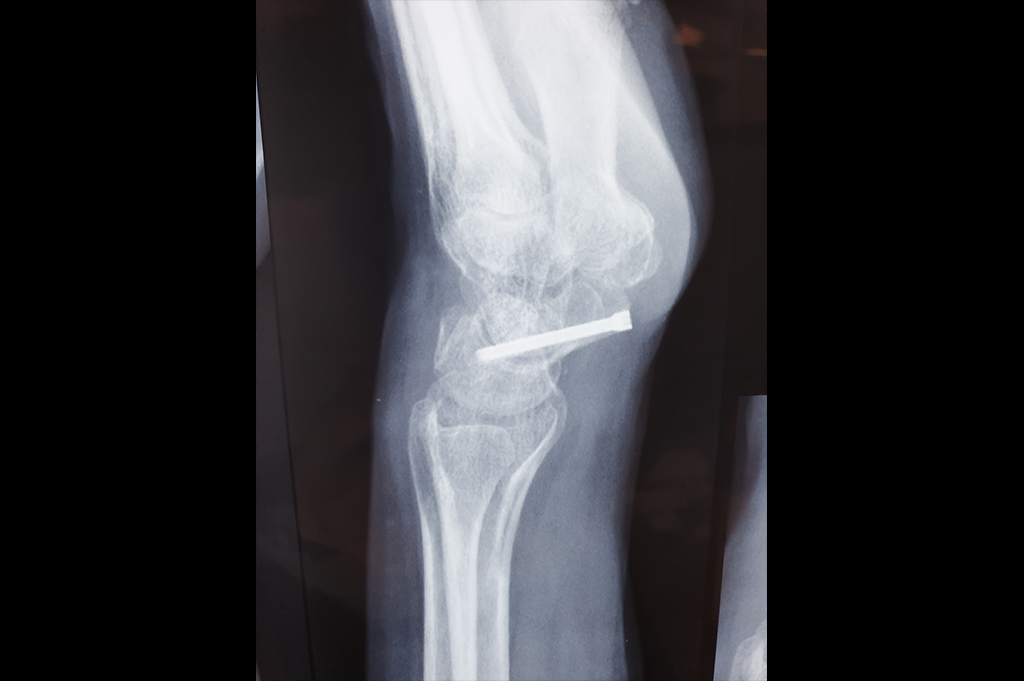

Elbow

Scaphoid